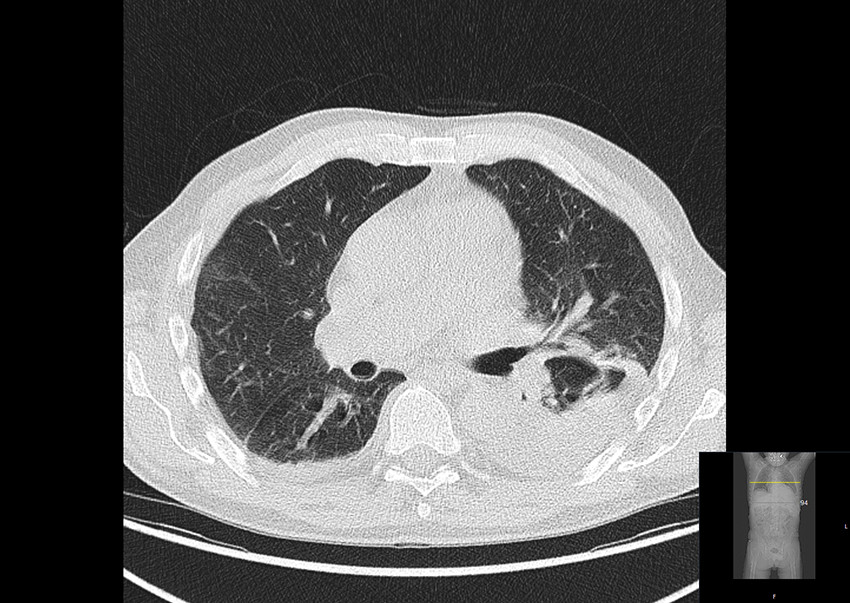

There was also increased uptake of 18F-fluorodeoxyglucose in bone marrow and lymph nodes, which were considered to be reactive changes. In addition, an infiltrate in the lower lobe of the left lung and pleural effusion were also found (Figure 2).

Giant cell arteritis affects people over the age of 50 years, and the annual incidence in Southern Norway is estimated to be 16.8 per 100,000 in the age group ≥ 50 years (4). Pulmonary opacities are not common in this disease. Other causes, such as malignancy and infection, could not explain the findings in the large blood vessels and were considered unlikely. Good response to treatment with prednisolone supported the diagnosis of giant cell arteritis.